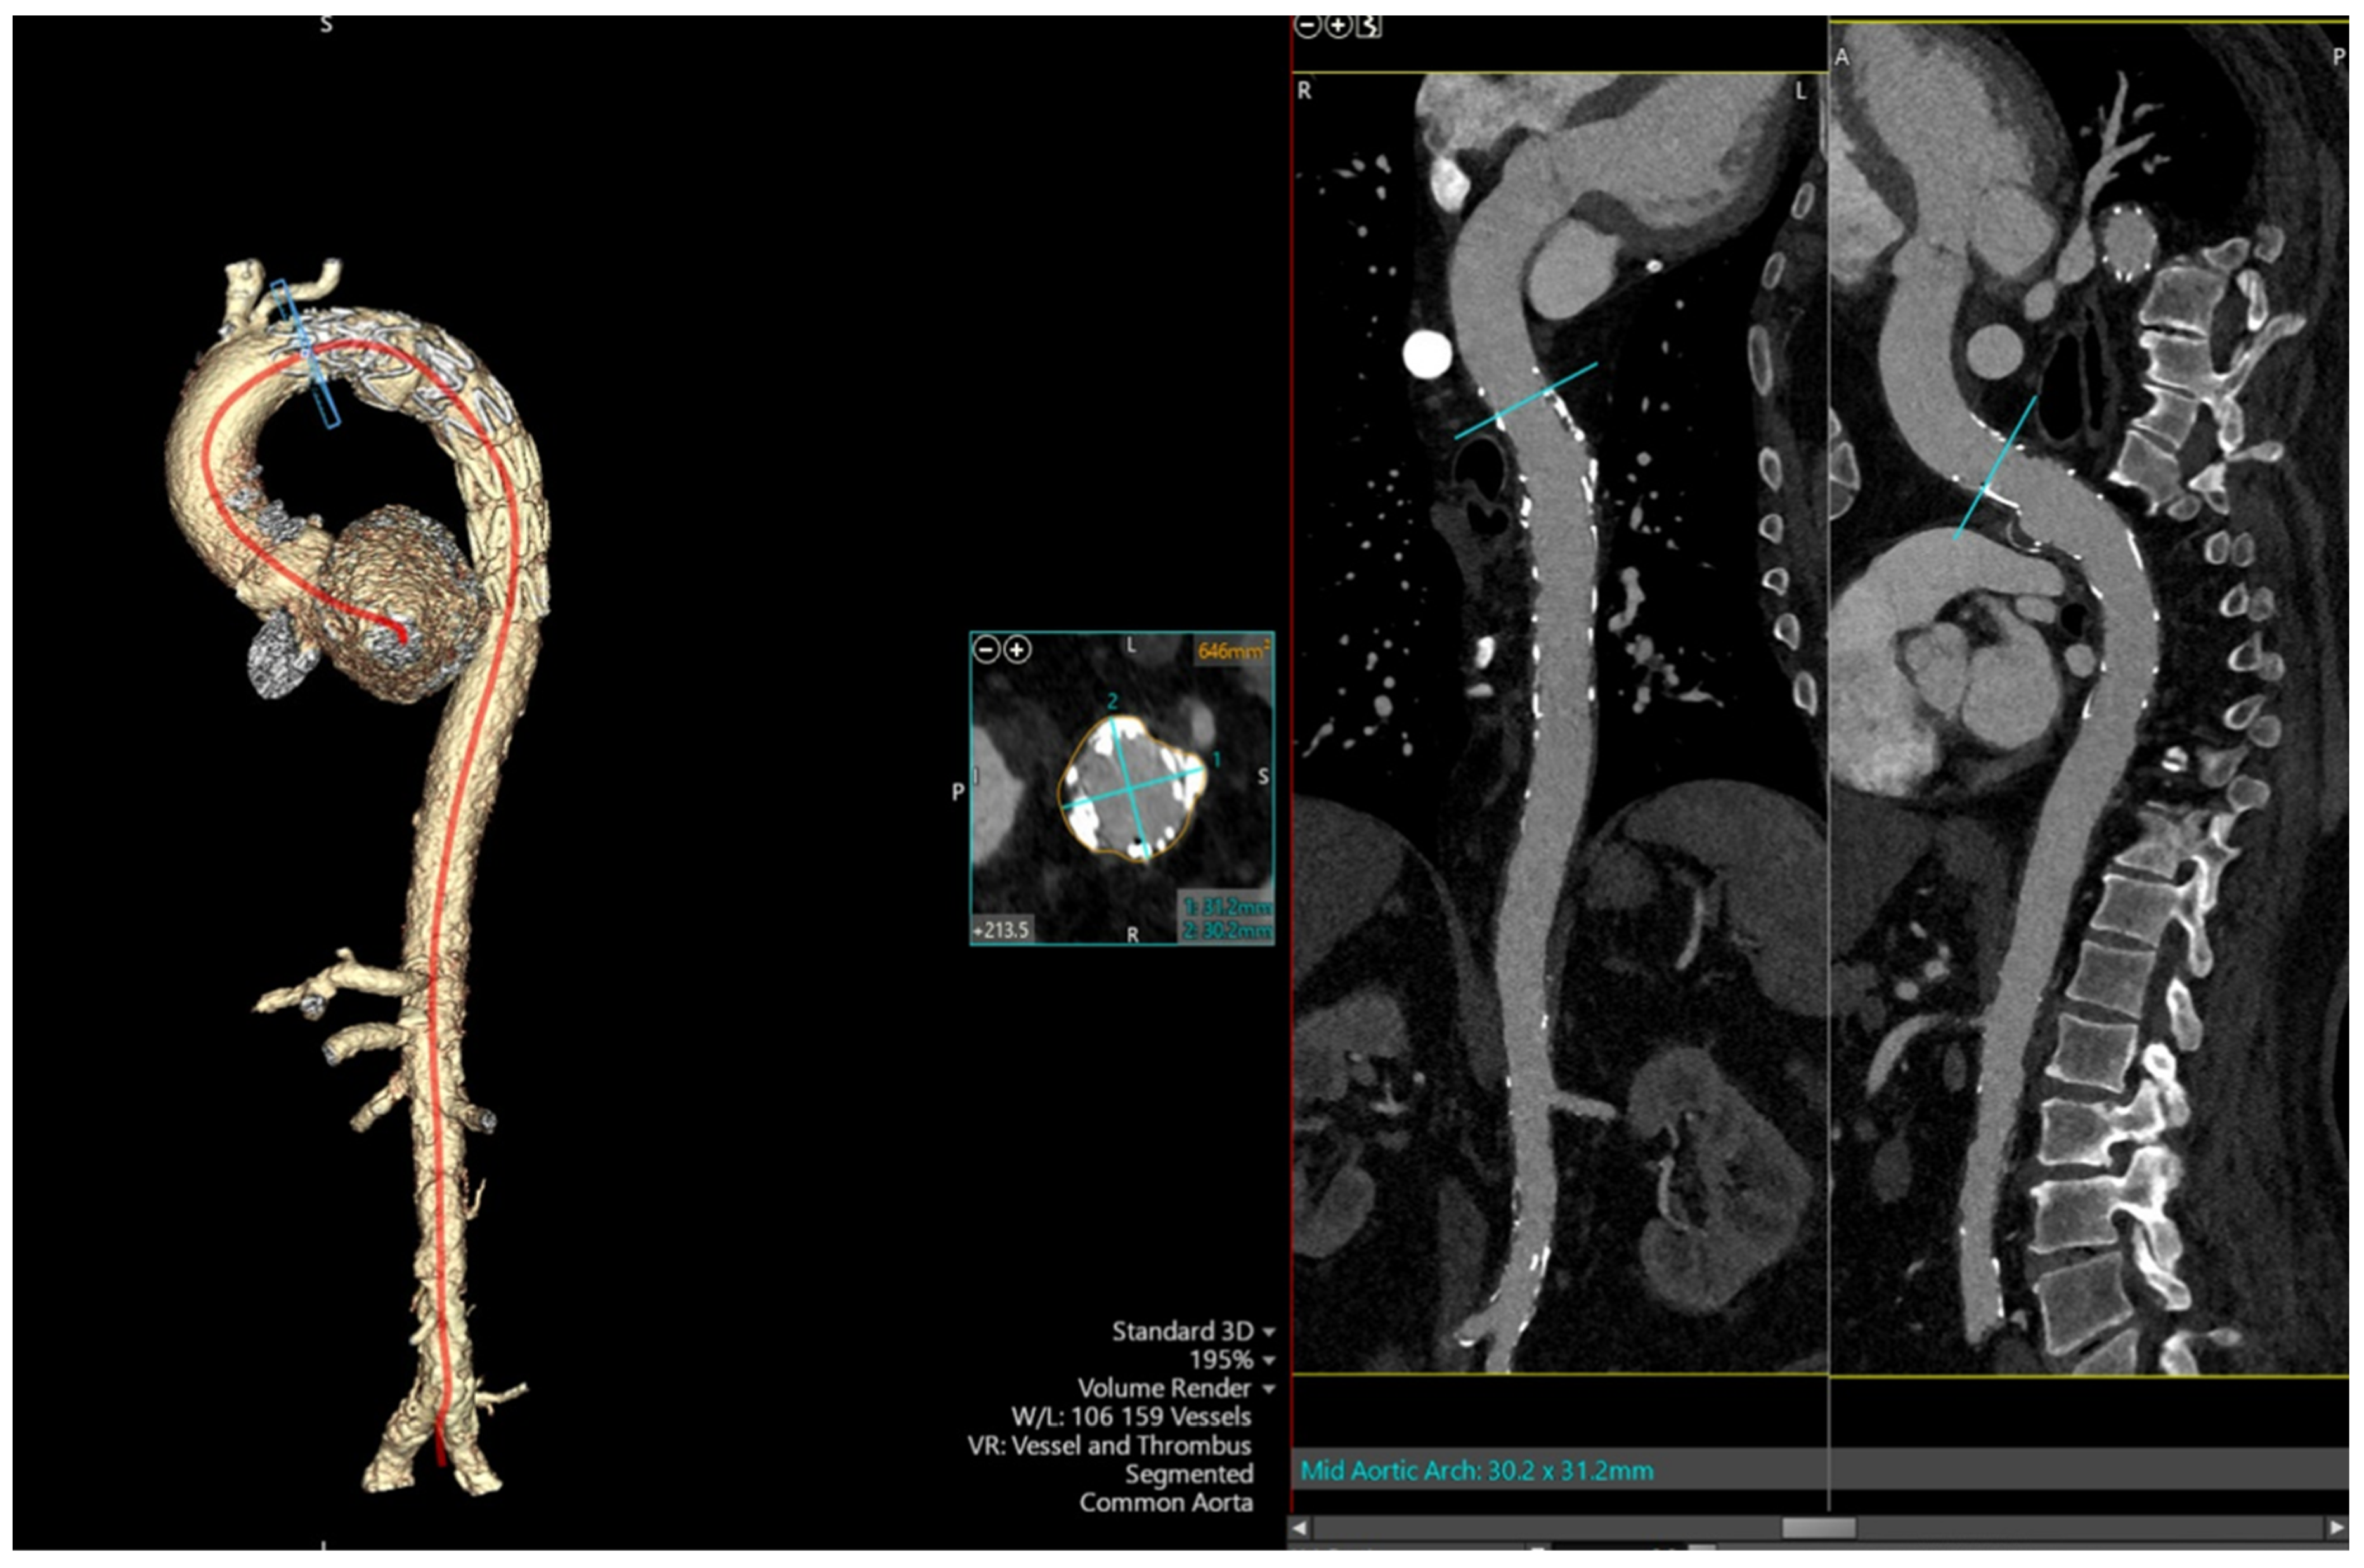

2. Case Presentation